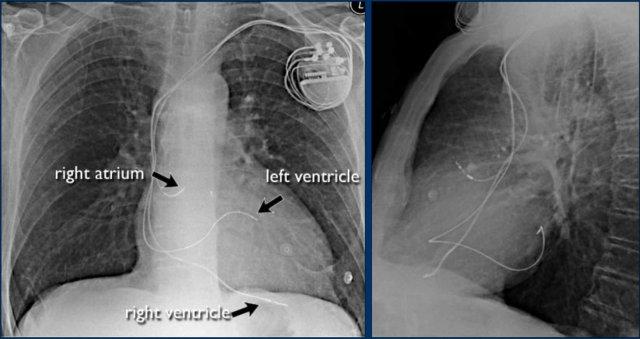

Máy Tạo Nhịp Tim

Có nhiều loại thiết bị tạo nhịp tim khác nhau, mỗi loại có cấu hình điện cực đặc trưng riêng.

Trong ví dụ này:

- Điện cực nhĩ phải

- Điện cực thất phải

- Điện cực thất trái qua xoang vành (sử dụng trong liệu pháp tái đồng bộ tim)

Chỉ định liệu pháp tái đồng bộ tim:

- Bệnh nhân có rối loạn đồng bộ thất được hưởng lợi từ tạo nhịp hai thất, giúp cải thiện sự phối hợp co bóp thất và tăng cung lượng tim.